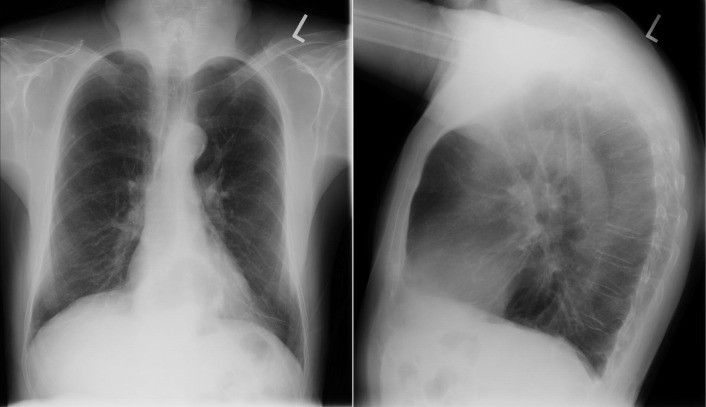

See Figures 18-5 to 18-31 . Possible findings are discussed in the following sections.

Left-to-right shunts initially result in volume overload of the chambers carrying the shunt volume, causing enlargement of the volume-overloaded chambers and an increase in pulmonary blood flow. If the amount of pulmonary blood flow is sufficiently high, obliterative disease of the pulmonary arterioles develops (“pulmonary vascular disease”), resulting in pulmonary hypertension. The chest radiographic appearance of pulmonary hypertension is one of centralization of pulmonary flow and accelerating enlargement of the right-sided chambers.